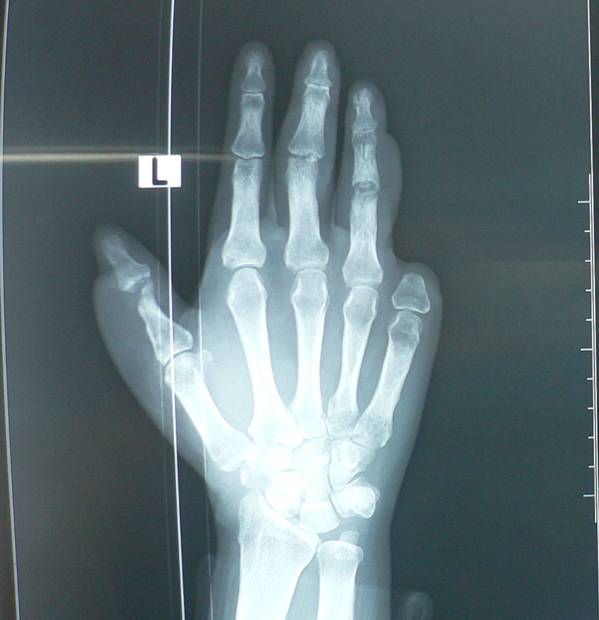

给你看两张片子,你就明白为什么不做肌腱移植了。拇指、示指、中指的关节都已经破坏吸收了。

伤后8个月